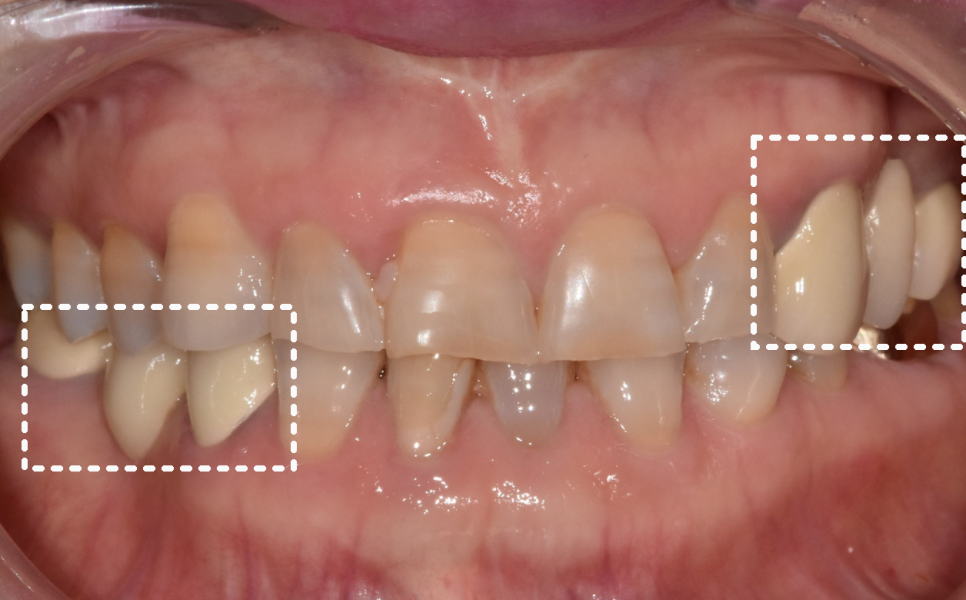

이 환자분은 누런 치아를 개선하기 위해

라미네이트를 문의하러 오셨습니다.

실제로 보니 치경부 쪽(치아와 잇몸 경계)이

전체적으로 어두웠습니다.

앞니 끝도 군데군데 깨져있었습니다.

하지만 그보다 더 큰 문제는

전체적으로 씹는 면이 많이 닳아있다는 점인데요,

이건 씹는 힘이 남들보다 강하다는 증거입니다.